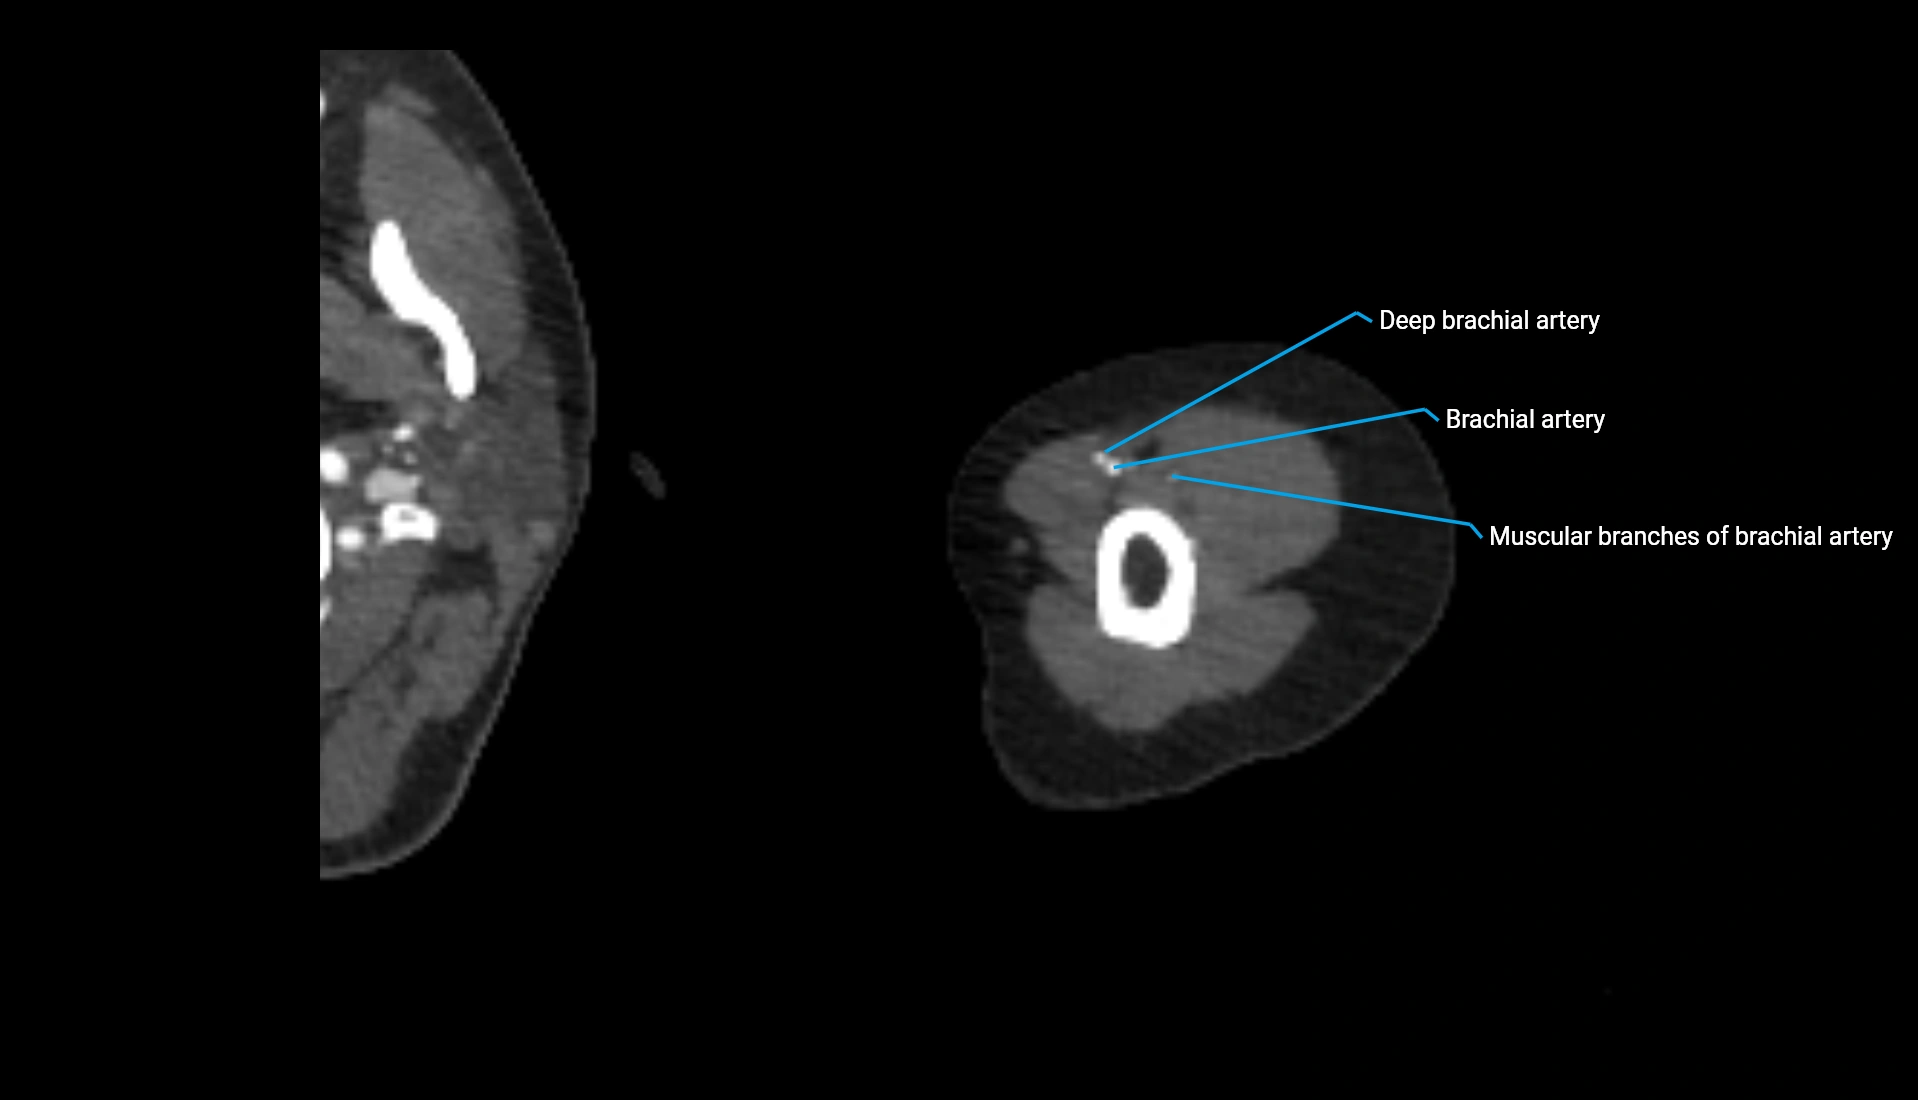

CT Appearance

Non-Contrast CT:

• Cortex: High-density, sharply defined

• Subchondral bone: Dense cancellous matrix

• Articular surface: Smooth concave contour articulating with the capitellum

• Excellent for evaluating bone integrity, alignment, and subtle fractures